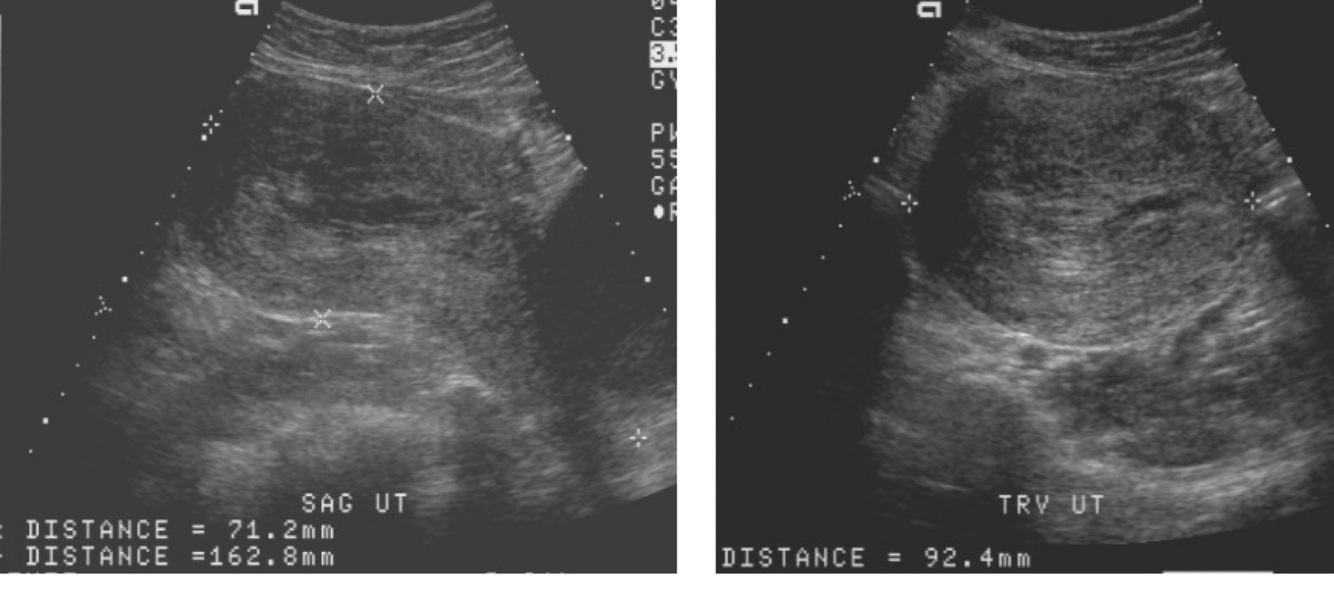

What does this image demonstrate?

A

Normal postpartum uterus

What is the normal postpartum uterus size?

Length 15-25 cm

What will we see with the normal postpartum uterus? 2

1. The uterus up to the maternal umbilicus

2. Prominent vessels